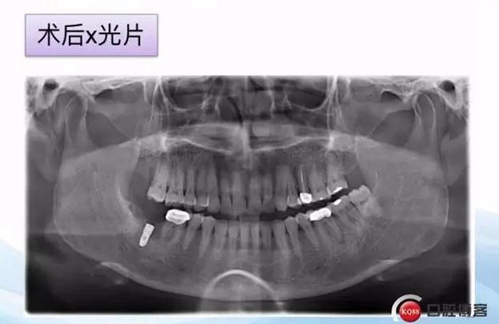

一例后牙常規(guī)種植病例 科貿(mào)嘉友收錄